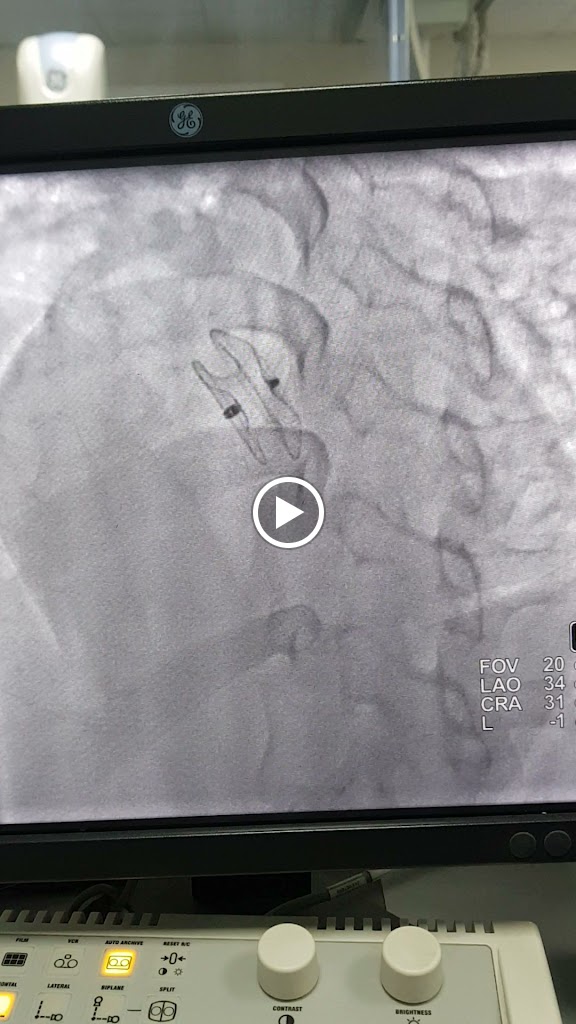

I have had a really good experience with Dr. Lekhraj. Last year(August 2023), I took both of my parents to Monikek hospital for a regular heart check-up. After doing 2D echo, doctor suggested angiography and after doing the procedure we got to know that my father had 80% blockage in his main coronary artery. I got panicked and was very sceptical around the angioplasty, but sir handled it pretty well and communicated the whole process properly. He performed the angioplasty and within 20 minutes, the procedure got completed. Dr Chaudhary was pretty professional during the whole procedure. It's been more than 6 months now and my father is doing well without any problem whatsoever. I am extremely thankful to Dr Chaudhary and his whole staff. He is now my go to doctor for all cardiovascular issues.